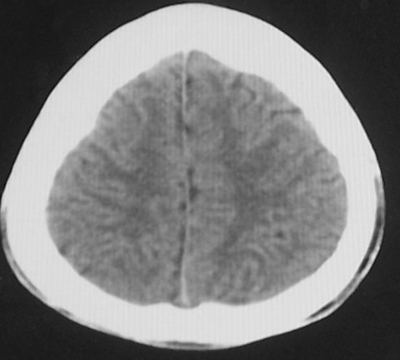

增强后

患者、男、18y,头痛5天入院。

左小脑、右丘脑区低密度影,无明显强化及占位表现,男18y,先考虑脑部炎性病变,如脑炎、血行播散性感染等,建议结合临床如脑脊液检验。

单独看左侧小脑半球的不规则形囊性低密度灶,从发病部位、年龄以及无强化、无占位效应的特点可以考虑毛细胞瘤型星形细胞瘤。同样,如果单独看右侧丘脑的近圆形低密度,也可以考虑囊变形星形细胞瘤。只是胶质细胞瘤一般为单发直接浸润、蔓延生长,而不是在脑内同时出现多个病灶,且瘤周没有一点儿水肿,暂时不予以考虑。

同时,现在已经进入冬天,一氧化碳中毒也需要考虑进去。不知道增强是什么时间做的,与平扫间隔几天?如果中间时间比较久而且进行吸氧等治疗,则平扫所示右侧颞叶密度比较低、右侧小脑半球以及脑桥也似有片囊状低密度,但在增强却没有发现就可以比较合理的解释了。

左侧小脑半球及右丘脑低密度影,考虑  1、脑梗塞灶. 2、占位性病变,建议作mri检查